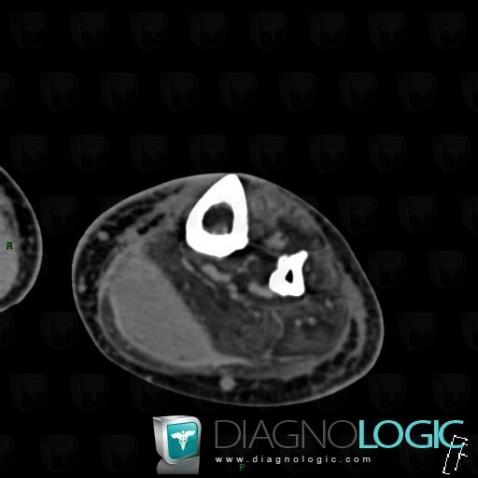

Here is the specific information in the key image above:

- Diagnosis Tennis leg , Location(s) Muscles - Leg, with gamuts

Here is the specific information in the key image above:

- Diagnosis Tennis leg , Location(s) Muscles - Leg, with gamuts